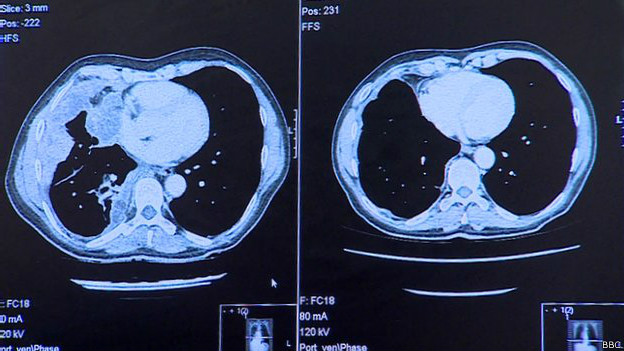

Los escáner de sus pulmones -como se muestra en la imagen- revelan que después de sólo tres infusiones, el medicamento pareció haber limpiado completamente el cáncer de su pulmón.

Antes de que empezara el tratamiento, apenas si podía hablar. El melanoma se había propagado a uno de sus pulmones, lo que le ocasionaba dificultades para respirar.